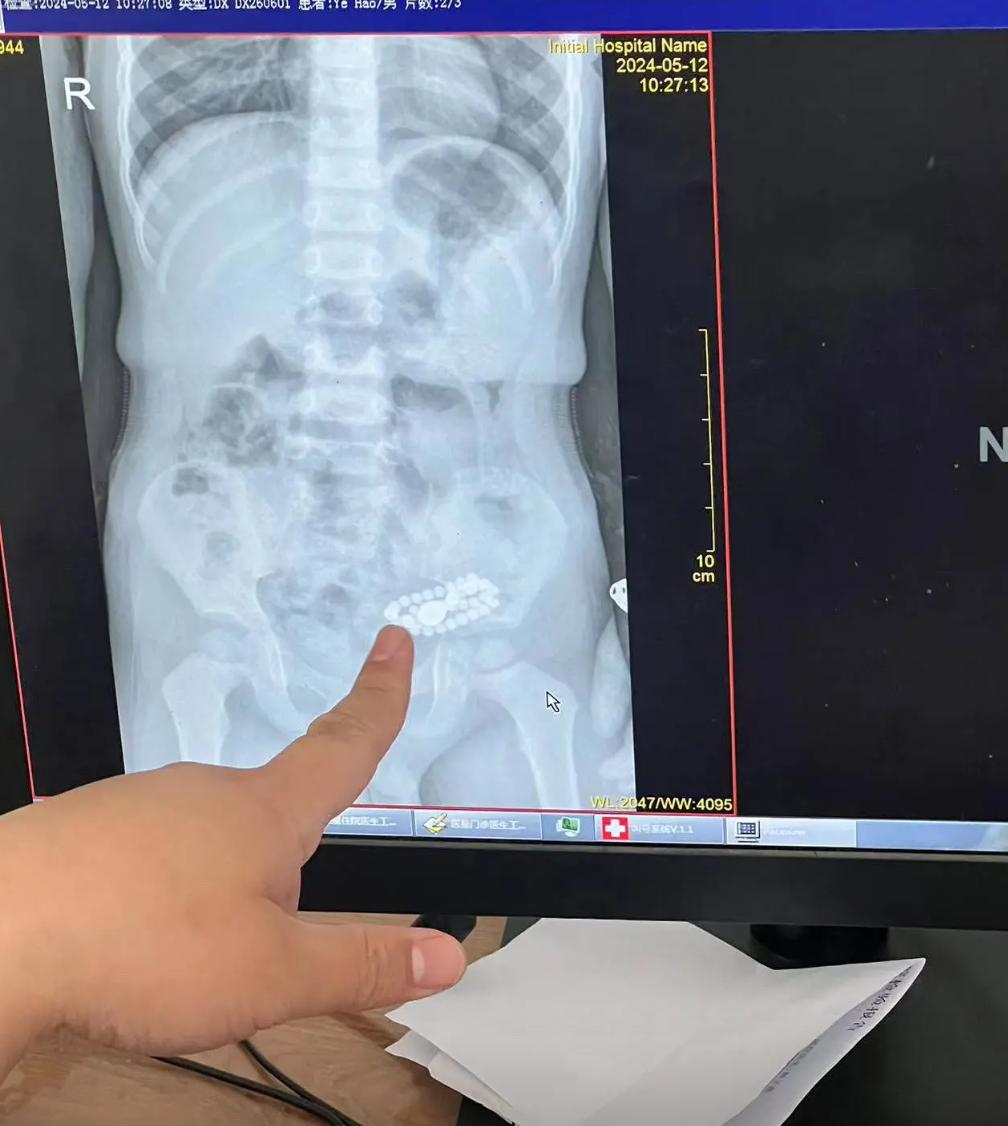

媽媽就半信半疑地帶着孩子去醫院做CT檢查,結果醫生給孩子做了個腹部CT,發現孩子的腸道里面就有一串金屬類的珠子,雖然不知道是不是媽媽的那串手串,但是看模樣就跟媽媽的那串手串一模一樣。

醫生說幸好沒有劃破胃腸什麼,而是在腸道里面,現在也沒有什麼可治的,先看看孩子能不能自己拉出來,回家讓孩子多喫一些,孩子喫得多就拉得多,拉得多就能把裏面的手串給拉出來,先看看情況,能拉出來就最好了。

也就是醫生建議家長不用在醫院治療,先回家讓孩子多喫一些東西,刺激孩子腸道的蠕動,然後讓孩子把手串給拉出來,媽媽就帶着孩子回家,讓孩子多喫一些膳食纖維多的,火龍果,玉米等等。